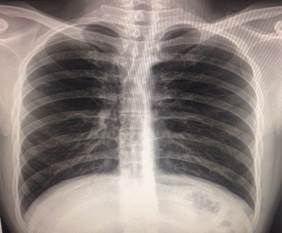

Es nuestro interés referirnos a un hombre joven suramericano de 23 años y a su problema de salud, este joven sin síntoma alguno consultó en un centro de asistencia médica de su país a un colaborador cubano; intentaba ingresar en la armada y acude para iniciar un chequeo médico necesario. El examen físico cardiocirculatorio fue inusual al igual que sus estudios imaginológicos donde aparecen y sorprenden por lo inesperado los hallazgos que más adelante se expondrán. Al final el paciente no necesitó de ningún tratamiento médico específico, solo recibió información detallada de la malformación congénita cardíaca y las medidas de prevención ante cualquier emergencia por esta anomalía cuyo nombre se conoce como ectopia cordisabdominal (ECA), no podría ingresar en la fuerza armada. Se le explica por qué no aparece la silueta cardiaca y vascular al rayo x (Rx) de tórax postero anterior (PA) (Figura 1).

Ni en la vista lateral (L) (Figura 2).